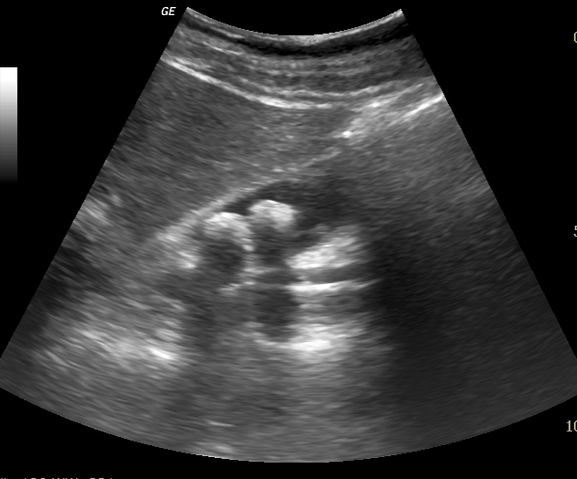

Image echographique

hyperechogene de deux calculs de la vesicule

biliaire . Cone de l'ombre sont en vue tres net |

|

Image de hypoascoustique posterieure de

calcul est toujour en se presentee . Meme cas

en un autre plan de coupe |

Lithiase vesiculaire multiple

situe a infudibulum de la vesicule biliaire .

L'ombre acoustique de vide posterieure est tres

large . |

Les petits calculs vesiculaire peut se

donne de images de artefact brilliant posterieure "

twinkle artefact " . cette artefact peut en voyait

meme sur les calculs renals , et de la vessi |